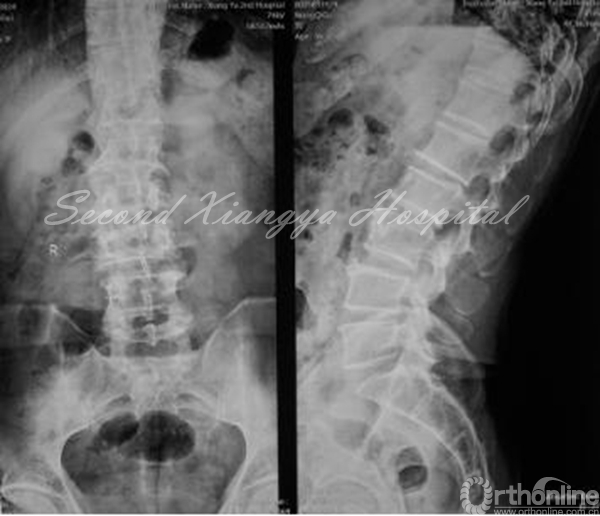

X线:动力位显示腰椎不稳。

术前正侧位片

动力伸位、动力屈位